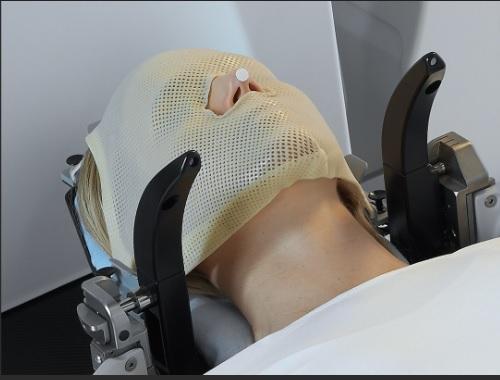

伽玛刀放射手术的原理,是先用磁力共振造影(MRI)及立体定位系统,精确地找出肿瘤的三度空间座标,再用特制头架(frame)或面罩(mask),把病人的头颅依座标值固定于伽玛刀仪器内,确定头部与仪器不会因为移位而产生误差,进而确保放射线准确聚焦在病灶上,而不伤及周边的脑结构。

伽玛刀放射手术由脑神经外科和肿瘤科一起执行,治疗前,先用MRI和电脑断层扫描(CT scan),配合立体定位技术,精确标记肿瘤的三度空间座标,再利用面罩,把娜娜的头颅依座标值固定,确保放射线准确聚焦。

由于肿瘤的体积不大,单次疗程就已足够,放射剂量为14Gy。治疗时,吴太太必须戴上头架,头架通过4个销钉连接到头骨,以便精确定位和稳定头部,接着,吴太太就躺在治疗床上,进入伽玛刀仪器中,在那里,头架会和仪器内的头盔牢牢固定在一起,放射线则从192个方向精确地照射到病灶上。

疗程长达4小时,中间吴太太可以稍作休憩,下床活动四肢,甚至上洗手间。为了让她放松心情,我们不时跟她说说笑笑,她苦笑着形容说戴头架好比孙悟空头戴金箍圈,虽然不痛,但也不太舒适,但她随即又暖暖一笑,道:“无论如何都比开刀好。”